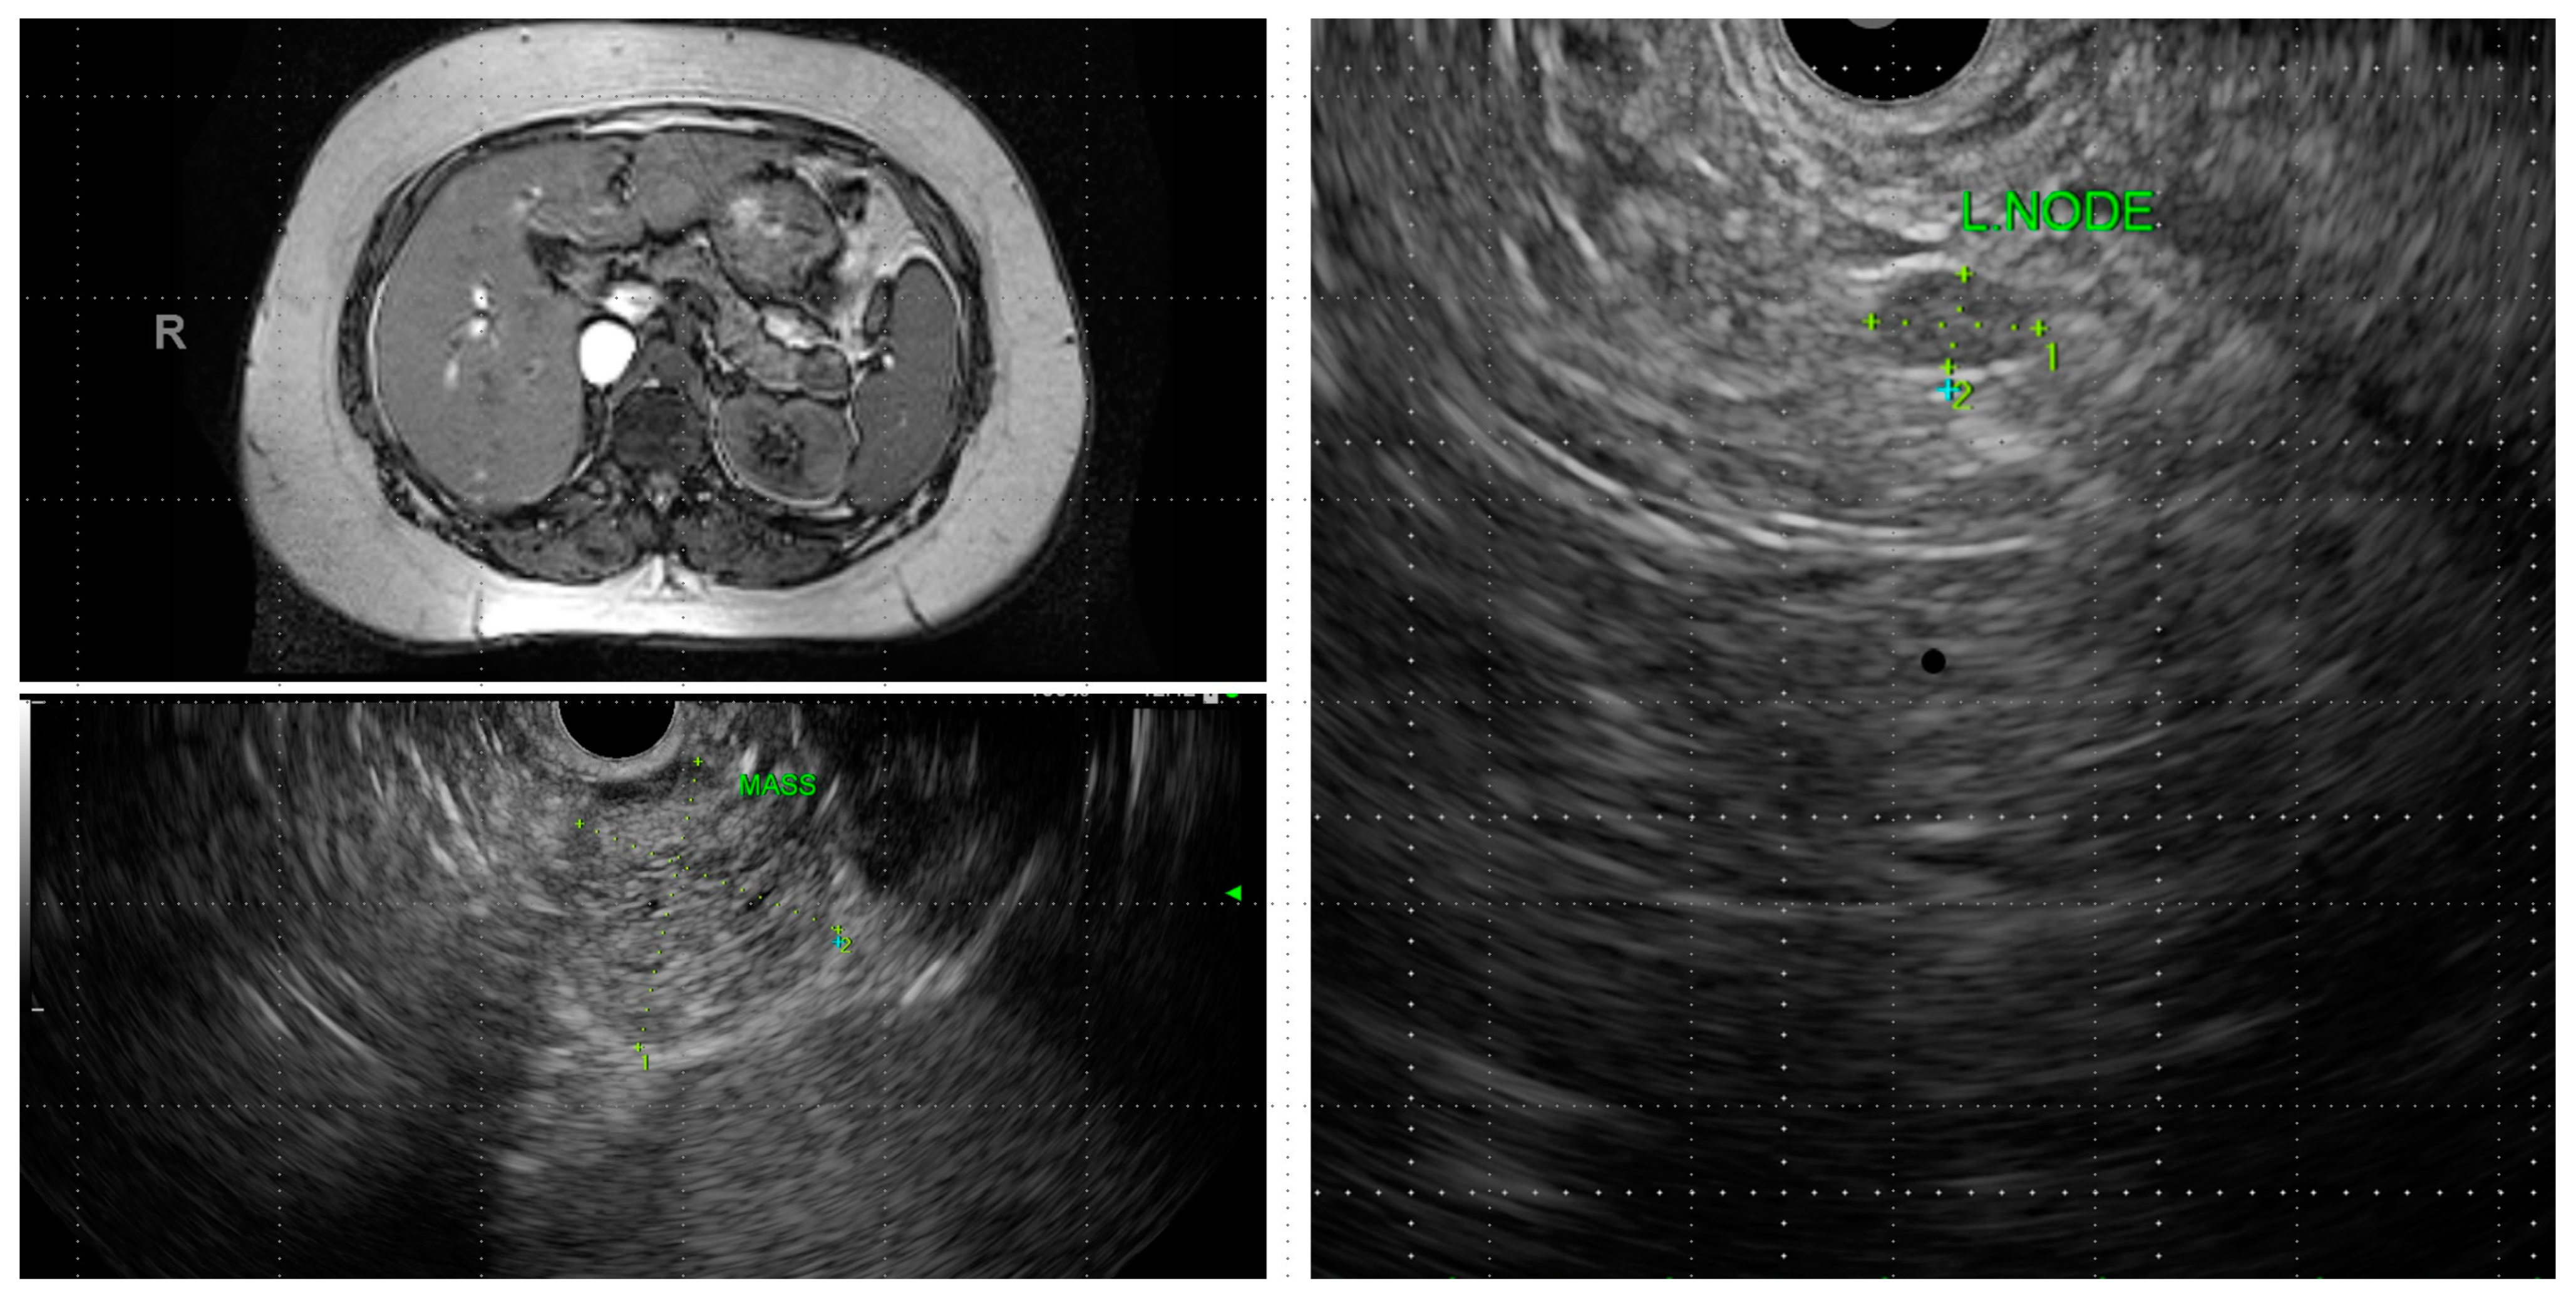

Figure 4.

MRI and endoscopic ultrasound demonstrating a solid pseudopapillary neoplasm involving pancreatic tail with a regional lymph node involvement.

Cyst morphology can provide some insights into the type when characteristic features are present. SPN are characterized by the presence of solid components in the form of a mural nodule. A noticeable feature of SCA, found in about a quarter of cases, is the presence of calcification within the cyst, and this is distinct from the peripheral calcification that can be seen in MCN and SPN (Figure 4). This is sometimes referred to as a “central scar.” Side-branch and mixed-type IPMN are multiloculated and appear as clusters, while main-duct IPMN usually does not demonstrate a prominent cyst but are seen on imaging as a diffuse dilation of the main pancreatic duct.

SPN: SPN are low-grade malignant neoplasms and usually run an indolent course. However, they carry the risk of metastatic spread, and liver and peritoneal deposits may be seen in 5–15% of cases (Figure 4) [17]. SPN is often diagnosed in young adults and are commonly present with an abdominal mass or abdominal pain, and are less commonly asymptomatic [18]. They are often well encapsulated and can potentially be cured with resection. Survival following surgical resection is non-inferior to people without SPN.